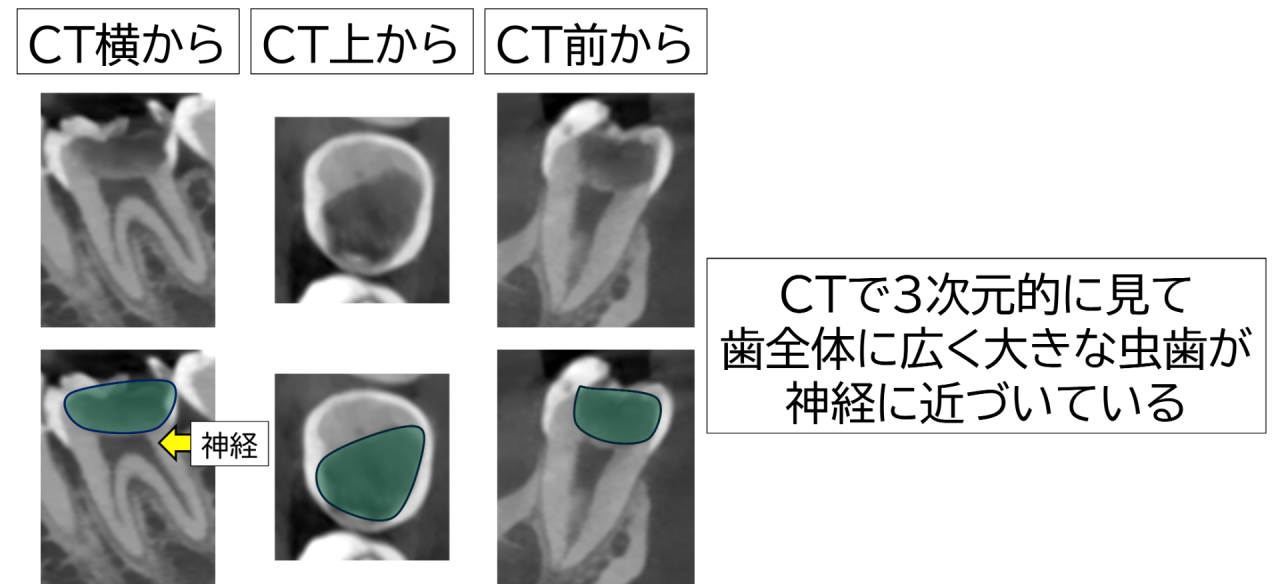

CTのレントゲンでは広く深い大きな虫歯が歯の中心の神経(歯髄)近くまで達している様に見えました。

所見から「深在性う蝕(=深い虫歯)、歯髄は生活反応あり(=神経はまだ生きている)」と判断。強く長続きする痛みが出ていないこと、レントゲン上で根の先に異常像がないことから、今回は神経を抜かずに残す治療を検討しました。

高倍率ルーペと歯科用顕微鏡(マイクロスコープ)を使用し、う蝕検知液や触診を頼りに虫歯を慎重に除去。健康な歯質を不必要に削らないよう、境界を一つずつ確認しながら進めました。予想通りではありましたが、神経の先端部分が露出しました。